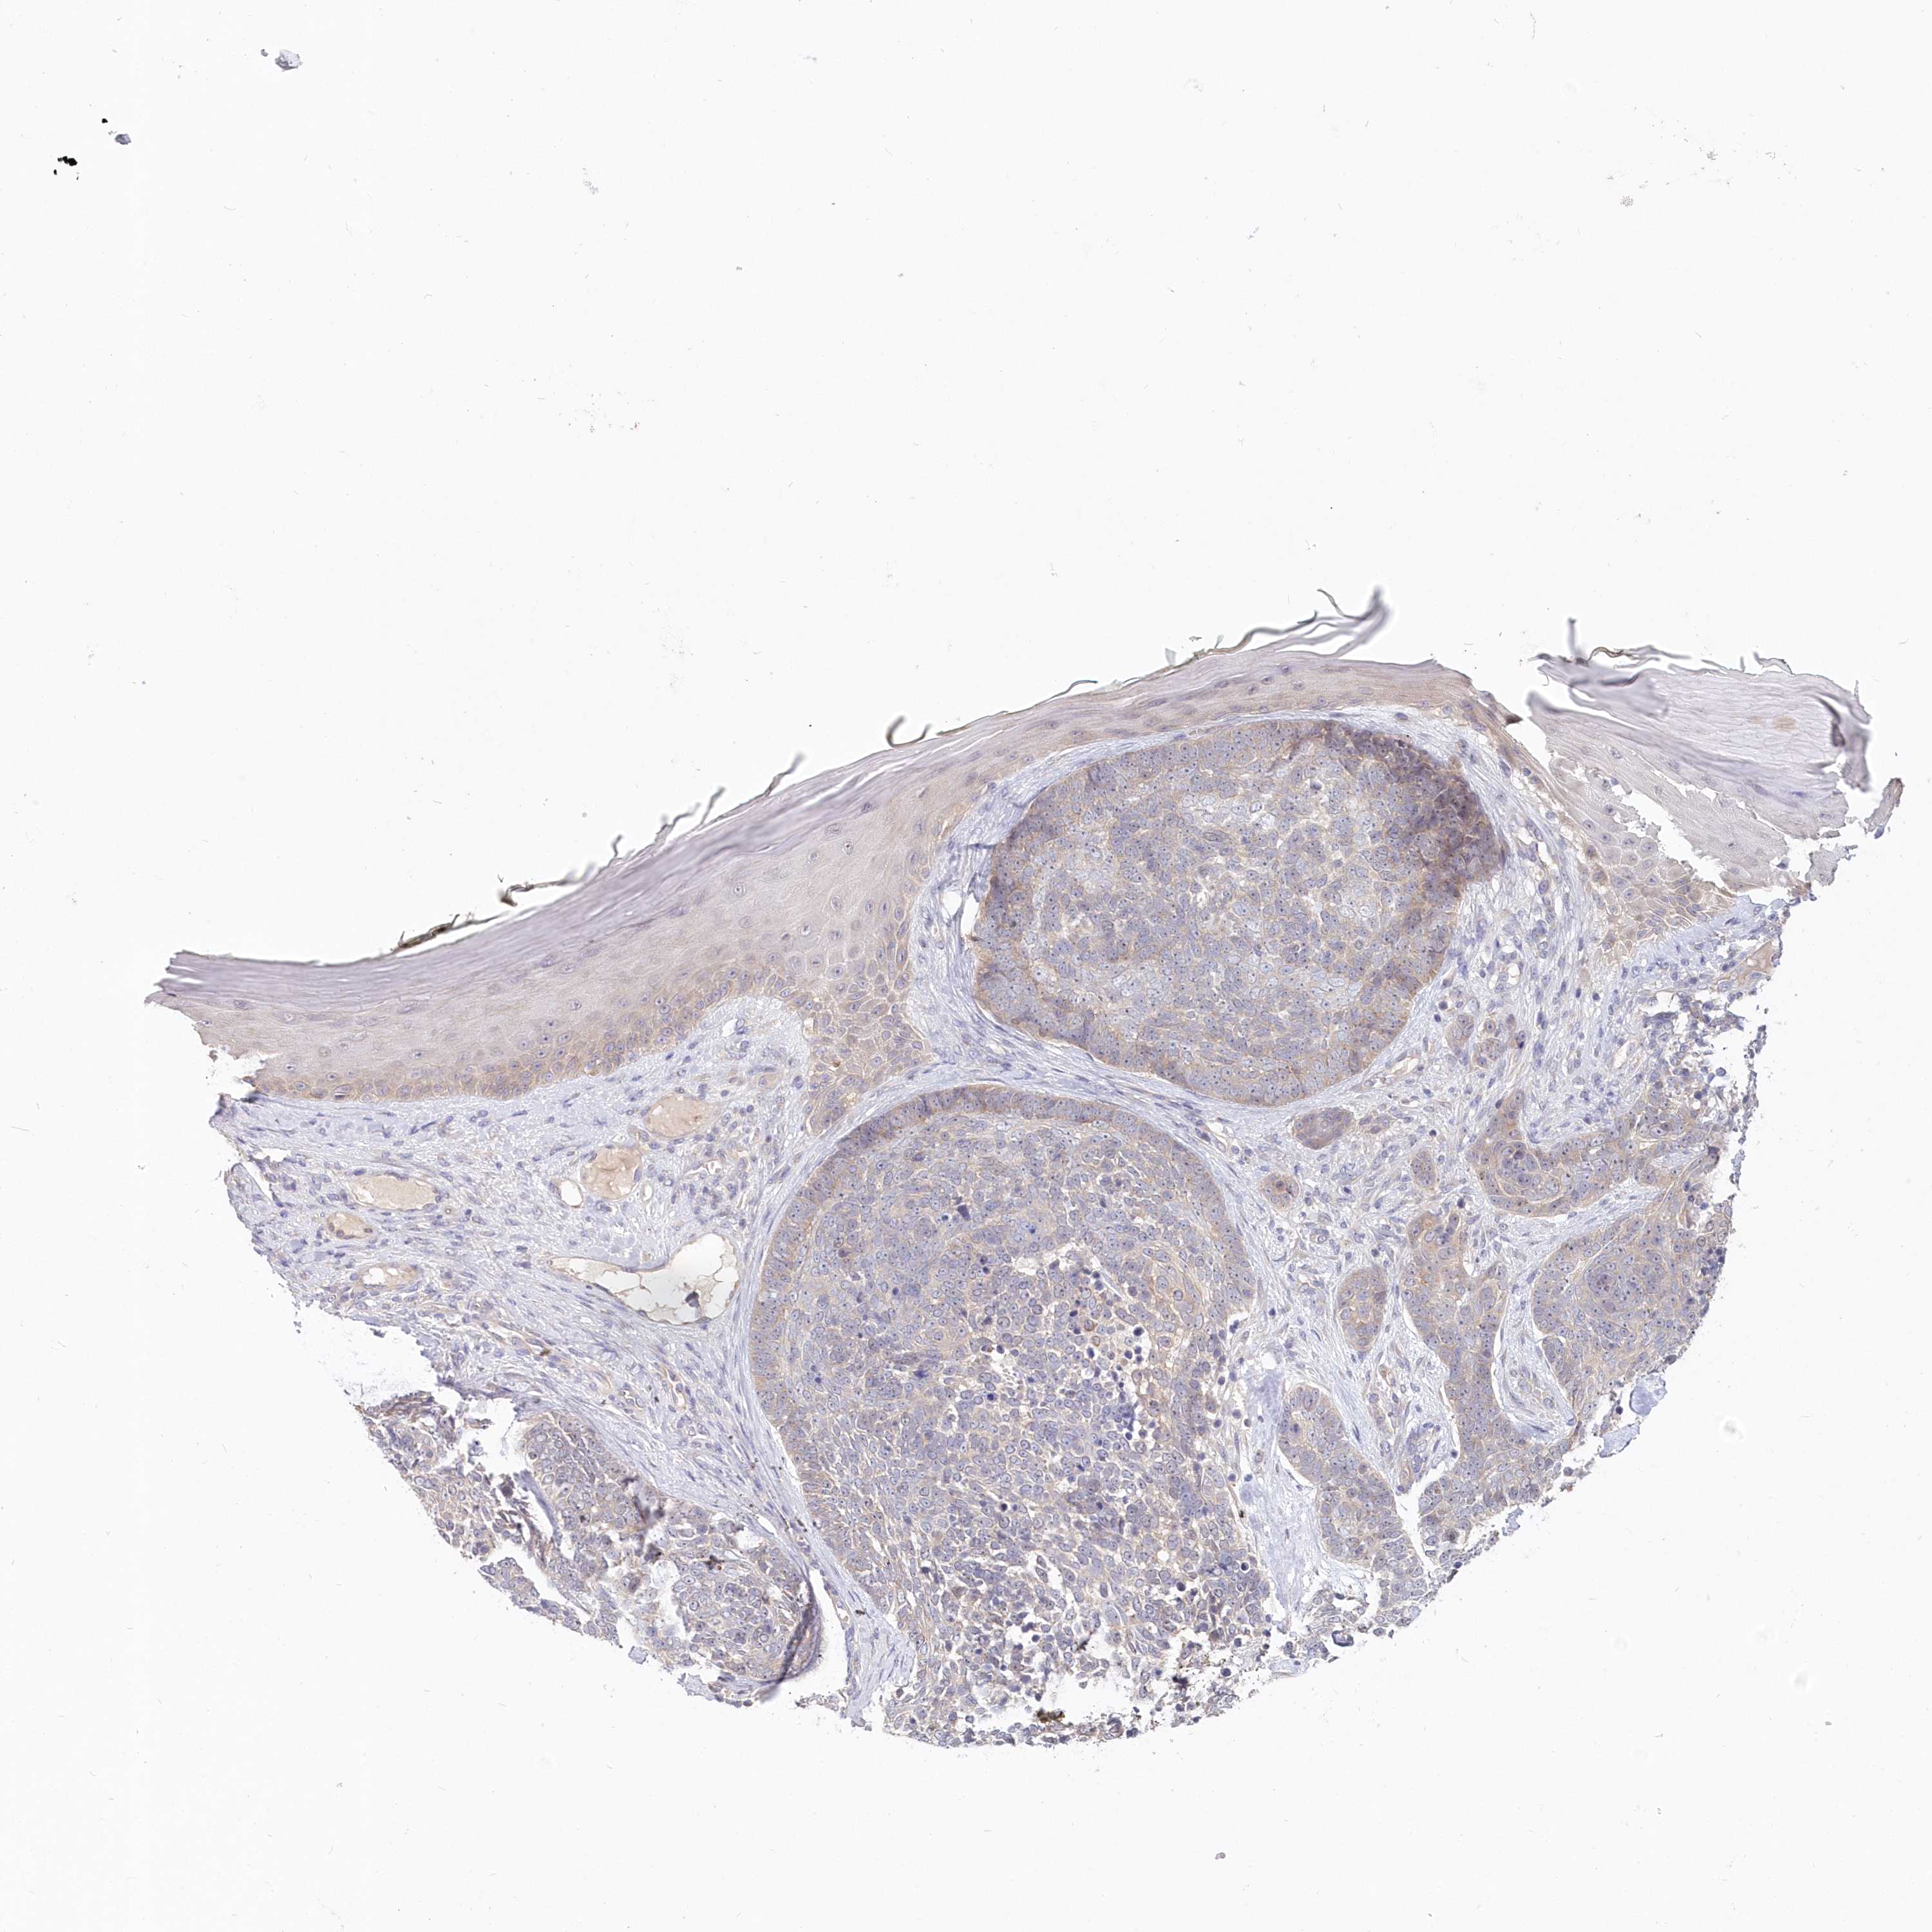

Basal cell and squamous cell cancer

SKIN CANCER - Protein expressioni

A mouse-over function shows sample information and annotation data. Click on an image to view it in a full screen mode. Samples can be filtered based on level of antibody staining by selecting one or several of the following categories: high, medium, low and not detected. The assay and annotation is described here.

Antibody stainingi

Antibody staining in the annotated cell types in the current human tissue is reported as not detected, low, medium, or high, based on conventional immunohistochemistry profiling in selected tissues. This score is based on the combination of the staining intensity and fraction of stained cells.

Each image is clickable and will lead to virtual microscopy that enables deeper exploration of all samples and also displays staining intensity scores, fraction scores and subcellular localization as well as patient and tissue information for each sample.

Antibody HPA036207

Staining

High

Medium

Low

Not detected

Intensity

Strong

Moderate

Weak

Negative

Quantity

>75%

75%-25%

<25%

None

Location

Nuclear

Cytoplasmic/membranous

Cytoplasmic/membranous,nuclear

Basal cell carcinoma